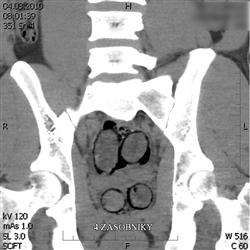

Olomoučtí celníci prováděli ve čtvrtek 4. března v nočních hodinách kontrolu mezinárodního rychlíku. Ten jel z Polska do Rakouska. Všimli si jednoho z cestujících, který vykazoval indicie naznačující pašování drogy. Pocházel z oblasti západní Afriky a trvalý pobyt měl v Evropské unii. Celníci provedli další kontroly za účelem detekce přítomnosti omamné psychotropní látky. Ty potvrdily výskyt drogy v těle. Následné CT vyšetření s jistotou prokázalo, že muž ukrývá v tělních dutinách čtyři kontejnery s neznámou látkou. Po vyloučení těchto předmětů z těla, za přítomnosti celníků, byl proveden drogový test a orientační vážení. Pasažér převážel v tělních dutinách 114 gramů kokainu. V lednu byl odhalen podobný případ, kdy cizinec přepravoval stejným způsobem 160 gramů kokainu.